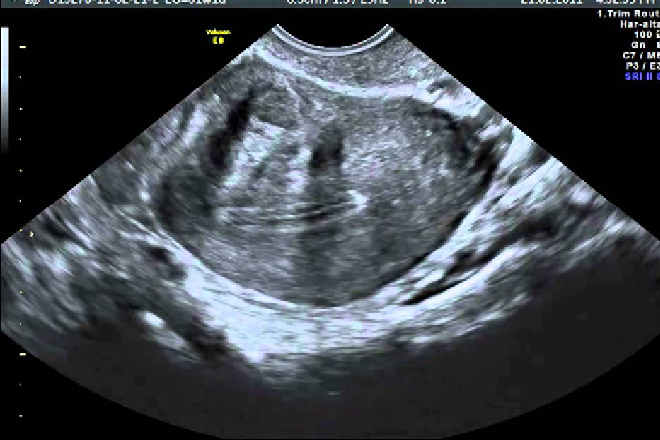

Su representación morfológica consiste en aumento de las dimensiones del útero, con pérdida de la homogeneidad de la ecogenicidad uterina y en ocasiones la ondulación del contorno del útero.

Los leiomiomas son las neoplasias más frecuentes del útero, presentes en la tercera parte de las mujeres en la cuarta década de la vida. Es la causa más común de aumento del tamaño del útero ante la ausencia de gestación.

1. Los miomas intramurales o miometriales, son los más frecuentes y son los responsables predominantemente, del crecimiento uterino. Provocan primeramente el aumento del diámetro anteroposterior del útero, confiriéndole forma esferoidal.

2. El contorno ondulado del útero es debido a la presencia de miomas subserosos. En ocasiones los miomas subserosos son sésiles pero pueden ser también pediculados, simulando tumores anexiales o no relacionados con el útero.

En la práctica ultrasonográfica, los hallazgos de miomatosis, como ya se mencionó, consisten en:

• aumento de tamaño del útero, usualmente a expensas de su diámetro anteroposterior (20-30% de aumento).

• heterogeneidad de la ecogenicidad uterina y contorno ondulado por la presencia de miomatosis subserosa.

• Los miomas submucosos alteran el aspecto del endometrio, deformándolo y modificando su ecogenicidad.